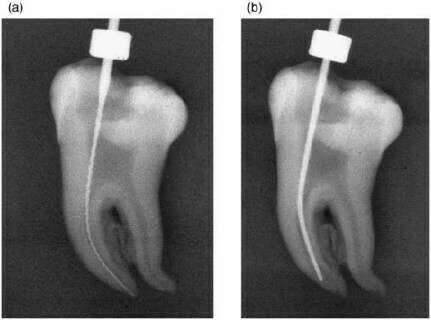

Trong hình minh họa bên dưới: Với răng cối lớn với ống tủy cong nhiều.

- (a) Phim X-quang ban đầu với trâm số #15, độ cong 42 độ.

- (b) Phim X-quang sau khi sửa soạn bằng trâm nickel-titanium số #40, độ cong 35 độ.

Như vậy kết quả của việc sửa soạn chỉ làm ống tủy bị dịch chuyển nhẹ về phía ngoài của đoạn cong mà thôi.